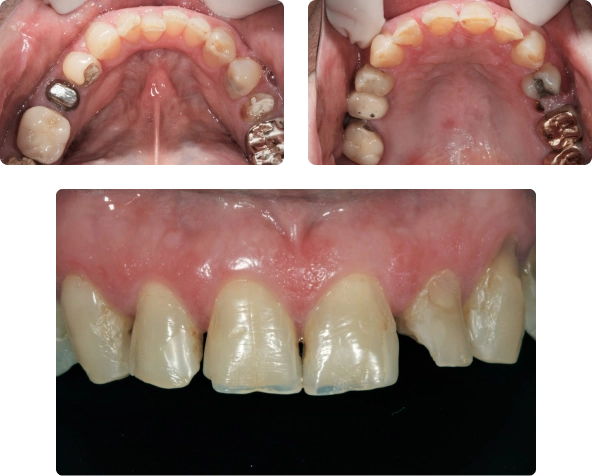

Antes

Quando chegou para a consulta inicial, ele já estava sem o aparelho e apresentava diversos problemas odontológicos, tais como: dentes cariados, quebrados, escurecidos, problemas periodontais e endodônticos (vários dentes com indicação para tratamento e retratamento de canais).

Propusemos um estudo, para o planejamento inicial, que consistia na confecção de modelos de estudo das arcadas superior e inferior, que foram montados em um articulador semi-ajustável (funciona como uma “maquete” do trabalho final), para a realização de um enceramento e diagnóstico, procedimento este que auxiliou no planejamento do tratamento a ser realizado.